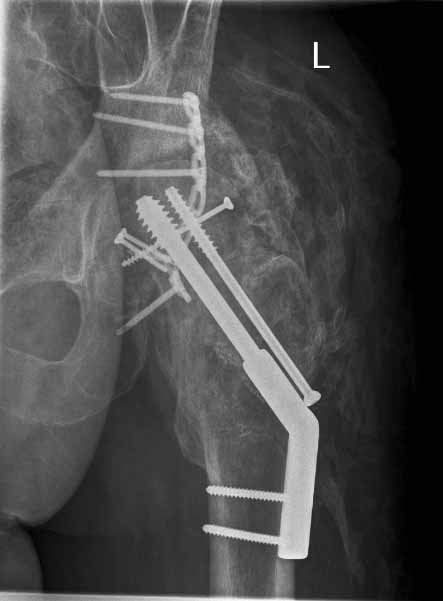

49 year old male, active speedskater, one year after MVC with multiple trauma and mild traumatic brain injury. Pipkin type IV fracture of the left hip. Same day ORIF through KL approach. No heterotopic ossification "prophylaxis". Day 7 wound revision for hematoma. Full weightbearing after 3 months. Full recovery except left hip function due to early severe HO. Function after one year: fixed ankylosis in 40 degrees flexion, 10 degrees exorotation. Patient frequently asks for attempt to improve hip function.

Post Op - Click to Magnify